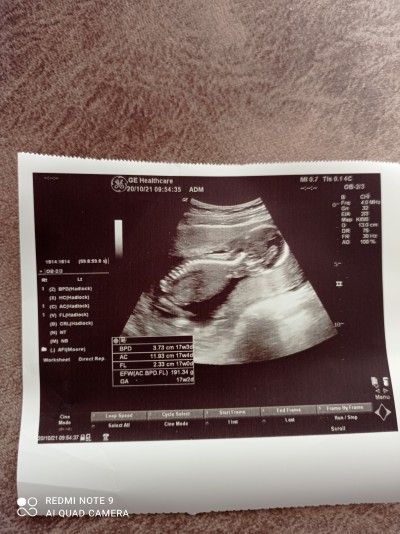

16 haftalık kızlar doktor pozisyon dan dolayı göremedi tahmin de yapmadı merak işte tahmin edebilen varsa yapabilir mi

Gebelik haftası 16+1 gebelik